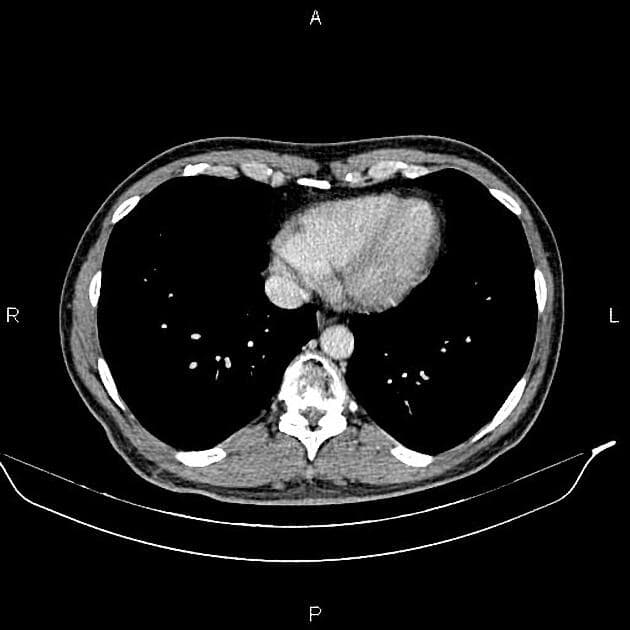

- Một khối nang khu trú một phần lồi ra ngoài (exophytic) kích thước 48 mm, thành dày ngấm thuốc (enhancement) và có các vách ngăn cùng các nốt ngấm thuốc lệch tâm (eccentric enhancing nodules) được ghi nhận ở phần giữa của thận phải.

- Ngoài ra, thấy một vài nang đơn thuần (simple cortical cysts) ở vỏ thận hai bên.

Khối nang thận - phân loại Bosniak IV (Renal cystic mass - Bosniak class IV)

- "Các đặc điểm hình ảnh chính bao gồm thành dày ngấm thuốc, vách ngăn ngấm thuốc và các nốt ngấm thuốc lệch tâm."

- "Phẫu thuật cắt bỏ (cắt thận bán phần hoặc toàn phần) là phương pháp điều trị tiêu chuẩn cho tổn thương Bosniak IV."